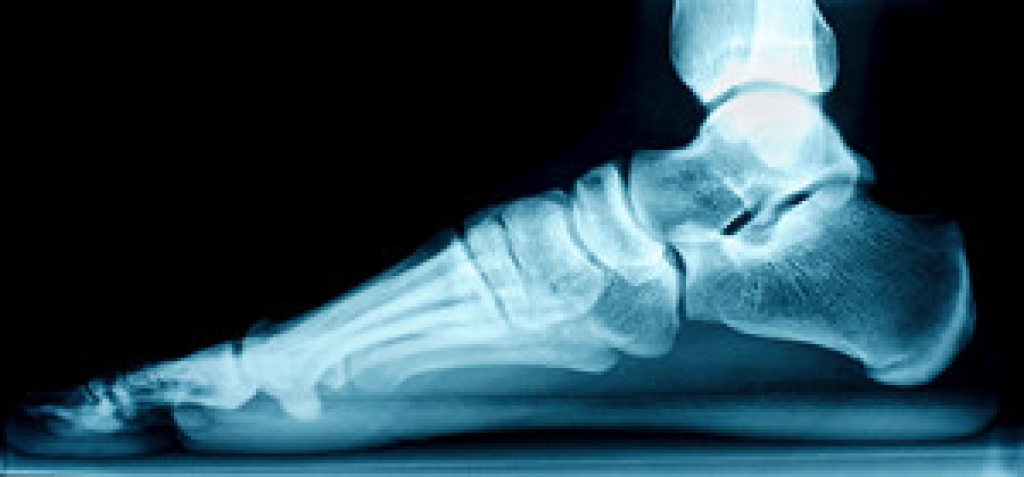

Foot biomechanics refers to the study of the structure, function, and motion of the feet. The feet and ankles are a complex system consisting of many bones, joints, ligaments, muscles, and tendons that work together to move your feet. Understanding the unique biomechanics of your own feet can help you and your chiropodist make informed decisions about your foot health care. This includes decisions about the best preventive measures to avoid foot pain, the best treatment options for various foot problems, and finding the best shoes for your feet.